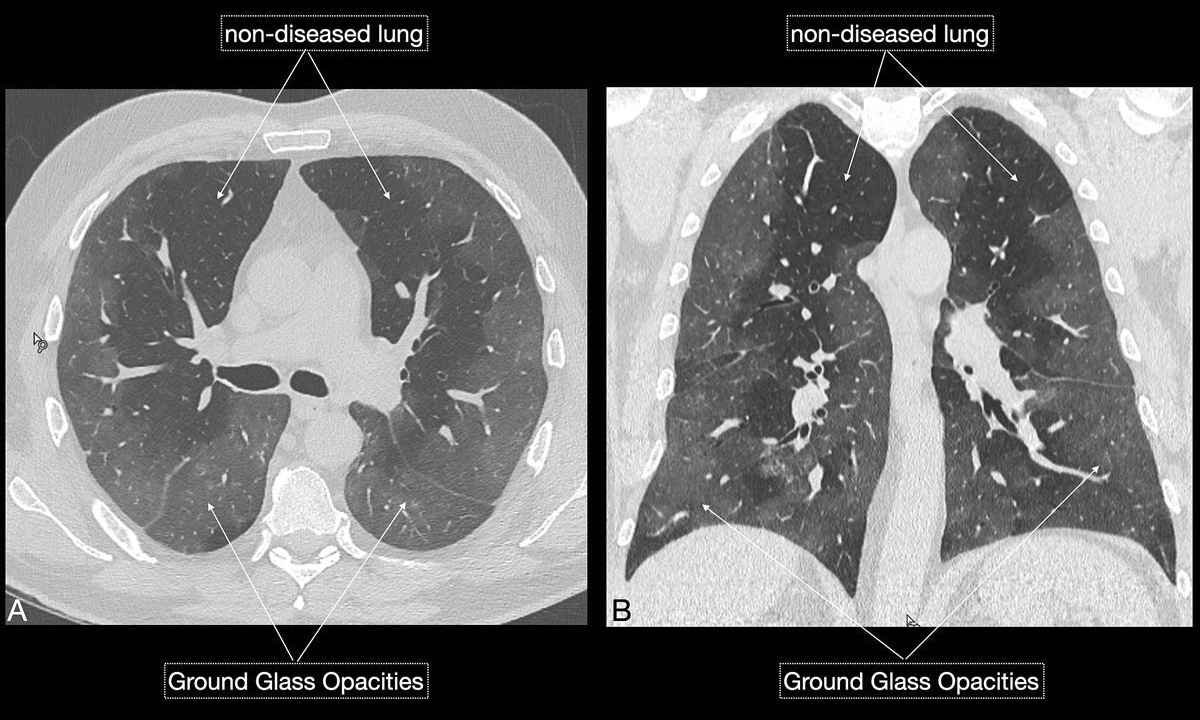

Figure 3 AB A 57-year-old male patient with cough, fever, myalgia and arthralgia for approximately 10 days was admitted to the emergency department. Laboratory work revealed lymphopenia, elevated lactate dehydrogenase, C-reactive protein and D-dimers. SaO2 was 82% on room air. RT-PCT test was positive for COVID-19. Chest computed tomography (CT) (A, B) revealed extensive ground glass opacities (Total Severity Score of 13/20 suggests a severe and critical course). Fairly immediate respiratory exhaustion led to intubation.

Figure 3 CD Chest x-ray (C) revealed extensive peripheral ground glass opacities, which became more consolidated (D) over the next 5 days.